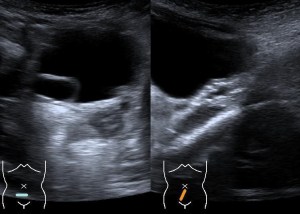

Bilateral duplicated collecting systems; ureterocele and megaureter (postnatal).

Unilateral hydronephrosis UTD A2-3.

Normal appearance of the fetal kidneys in the transversal plane at 31 weeks.